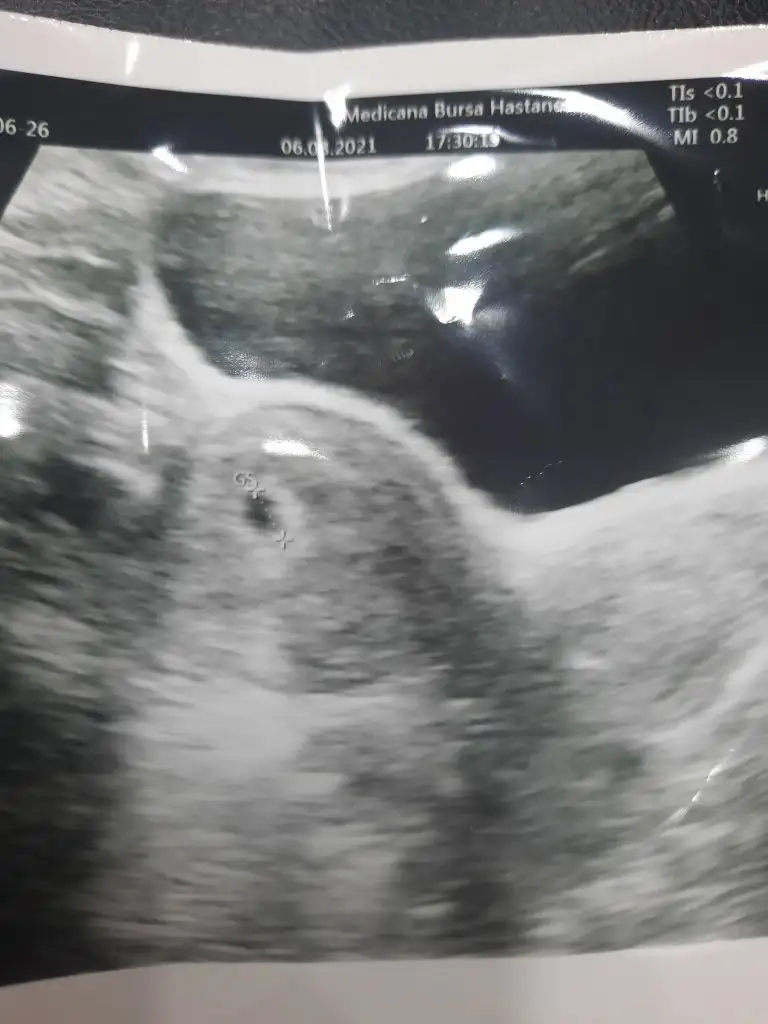

Hayırlı olsun, sağlıkla al kucağına :)Ben bugün keseyi gördüm, 5+3 müş, betamda 3400 çıktı. Haftaya tekrar gel dedi, kalp atışını duyabilir miyim acaba?

Ultrason resimlerini atmıştımİnsallah rahat geçiririz zaten bulantı vs zor ama Allah veriyorsa vardır bi bildiği, ohh ne güzel kacinci haftada duydunuz![]()